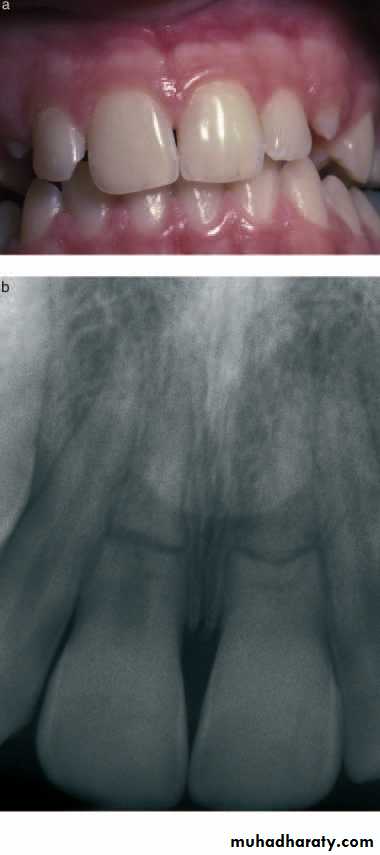

VISUAL AND TACTILE INSPECTION

Soft tissue:-Color- the normal color of gingiva is coral pink. Change from this is easily visualized in inflammatory conditions. Contour- change in normal contour (eg, of scalloped gingiva) occurs with a swelling. Consistency- On inspection (most commonly gingiva) appears healthy, firm, resilient, while a soft, fluctuant or spongy tissue is more indicative of a pathological state.Hard tissue:

Color- Normal teeth show life like translucency & sparkle that is missing in pulp less teeth which appear more or less opaque. Note: This discoloration however could be due to a variety of other reasons like old amalgam restorations, tetracycline stains etc.Contour- This examination should also include the visualization of contours of affected teeth, such as fractured teeth, wear facets, improperly contoured restorations, or altered crown contours as these factors can have a marked effect on the respective pulps.

Consistency- Change in the consistency of hard dental tissues is related to the presence of caries, external and internal resorption